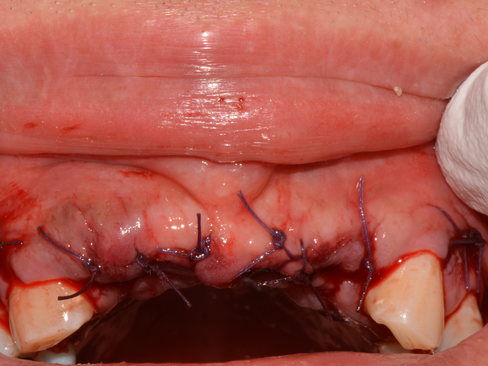

Periosteal splitting done for tension free primary closure.

Tension free primary closure with double sling suture.

Horizontal mattress suture and simple interrupted suture.